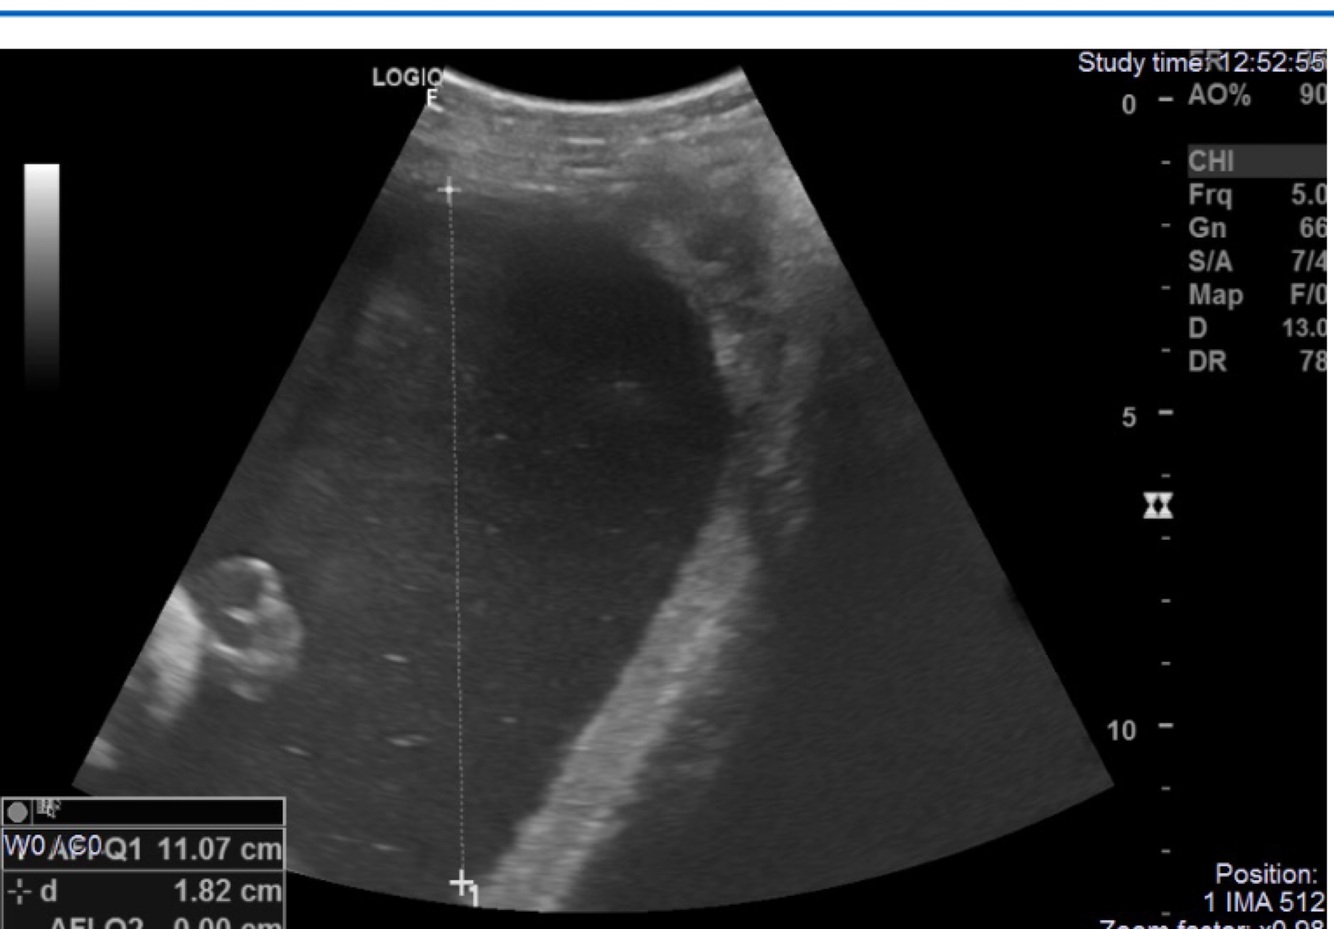

Q

What does this image demonstrate?

A

AFI measurements in the four quadrants